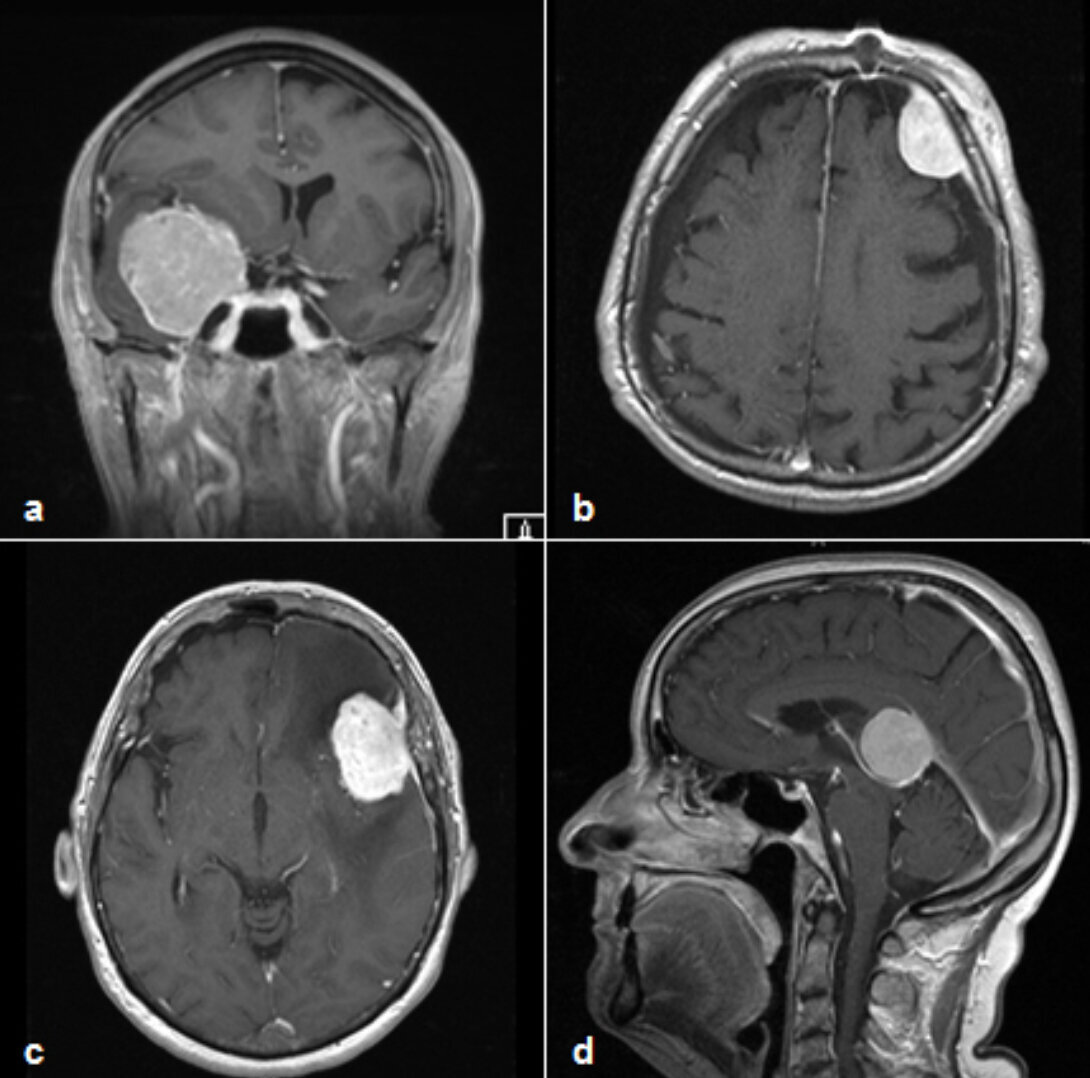

Die Diagnostik erfolgt durch CT- und MRT-Bildgebungen. Diese Bilder können auch während der Operation zur Neuronavigation genutzt werden, um den Tumor und umliegende Hirnstrukturen genau lokalisieren zu können. Je nach Befund können auch noch anderer Untersuchungen, wie z.B. eine Angiographie (Gefäßdarstellung), erforderlich sein.